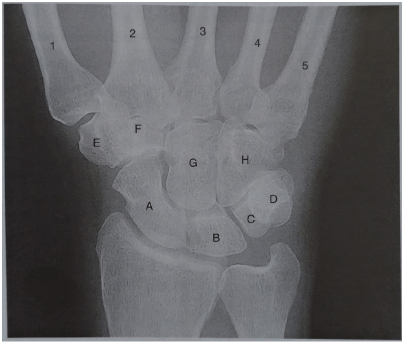

Associe as letras que estão no raios X em PA do punho com suas respectivas estruturas.

| ( 1 ) Capitato | ( ) A |

| ( 2 ) Semilunar | ( ) B |

| ( 3 ) Pisiforme | ( ) C |

| ( 4 ) Hamato | ( ) D |

| ( 5 ) Trapezoide | ( ) E |

| ( 6 ) Escafoide | ( ) F |

| ( 7 ) Trapézio | ( ) G |

| ( 8 ) Piramidal | ( ) H |

Marque a alternativa que tem a sequência CORRETA.